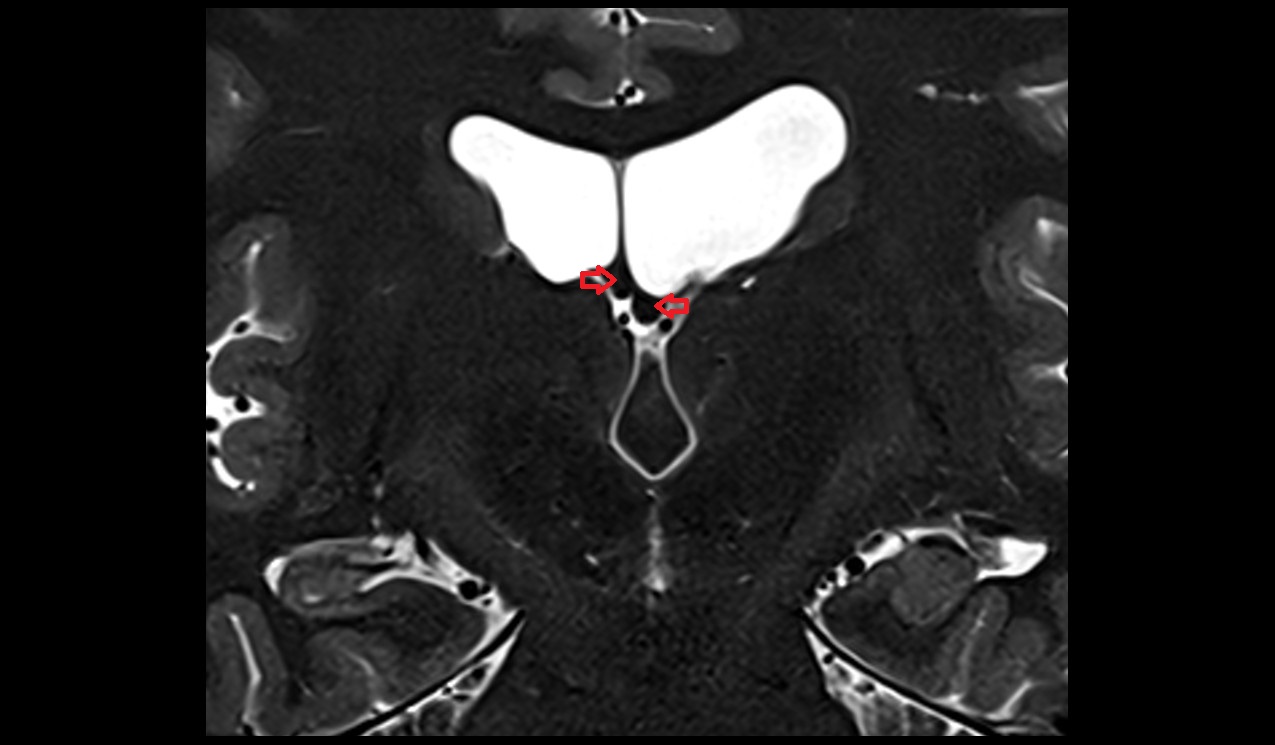

- Fetal brain

- Fetal lateral ventricle